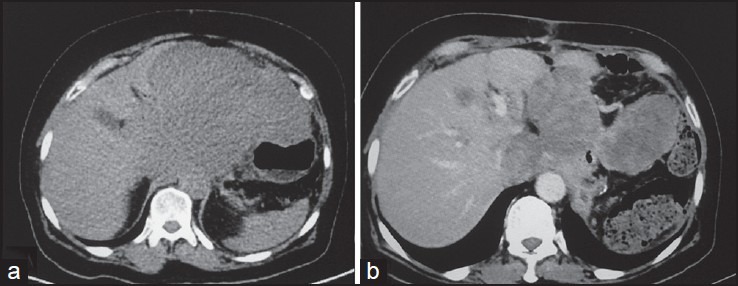

| Figure 16:Malignant metastatic stomach gastrointestinal stromal tumors posttreatment — (a) Axial noncontrast computed tomography scan showing heterogeneous mass arising from stomach and abutting the liver (b) posttreatment the mass shows heterogeneous enhancement with significant decrease in size

| Figure 16:Malignant metastatic stomach gastrointestinal stromal tumors posttreatment — (a) Axial noncontrast computed tomography scan showing heterogeneous mass arising from stomach and abutting the liver (b) posttreatment the mass shows heterogeneous enhancement with significant decrease in size

Complete surgical excision is the treatment of choice. Unlike carcinomas, resection of GISTs does not require wide bowel excision or lymphadenectomy as these tumors usually do not show lymph node metastases.[8] However, despite apparently complete resection with clear margins, the recurrence rate is high. Chemotherapy with imatinib mesylate, a tyrosine kinase inhibitor has been found to be highly effective in treatment of metastatic GIST. Imatinib mesylate has revolutionized the management of GIST. Now it is often used as the first-line treatment for unresectable, metastatic, or recurrent GIST. Although complete responses are rare, a large majority of patients with metastatic or inoperable GIST have either a partial response or disease stabilization after starting imatinib. Median survival rates have gone from <2>5 years since the advent of imatinib therapy.[11] Role of imaging also lies in response evaluation of patients treated with imatinib. Response to imatinib is characterized by decreased enhancement, resolution of the enhancing tumor nodules and a decrease in tumor neovascularity [Figures [Figures1616--20].20]. These changes are usually seen within 1-month of initiation of chemotherapy. Initially, tumors may enlarge during treatment due to intratumoral hemorrhage and myxoid degeneration. Enlargement with an overall decrease in tumor enhancement suggests a favorable response. Presence of new enhancing nodules within the tumor is consistent with recurrence.[12]